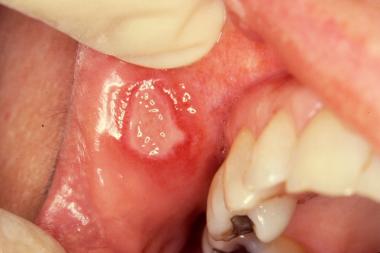

كثير من المراجعين يشتكون من #التقرحات التي تحصل في منطقة #الفم سواء داخل الخد او الشفاه الداخليه و ايضا على اللثة

تسمى Aphthous Ulcers وهي مزعجة جدا جدا لهم

مثل ماهو مبين في الصورة أسفل

يحصل Aphuous Ulcers او التقرح الحاصل داخل #الفم بسبب إختلال في جهاز #مناعة الإنسان مع شح في فهم مسبباتها الفعلية

#التقرح يحصل بالعادة في منطقة الخد و أسفل الفم و كذلك في داخل الشفايف.